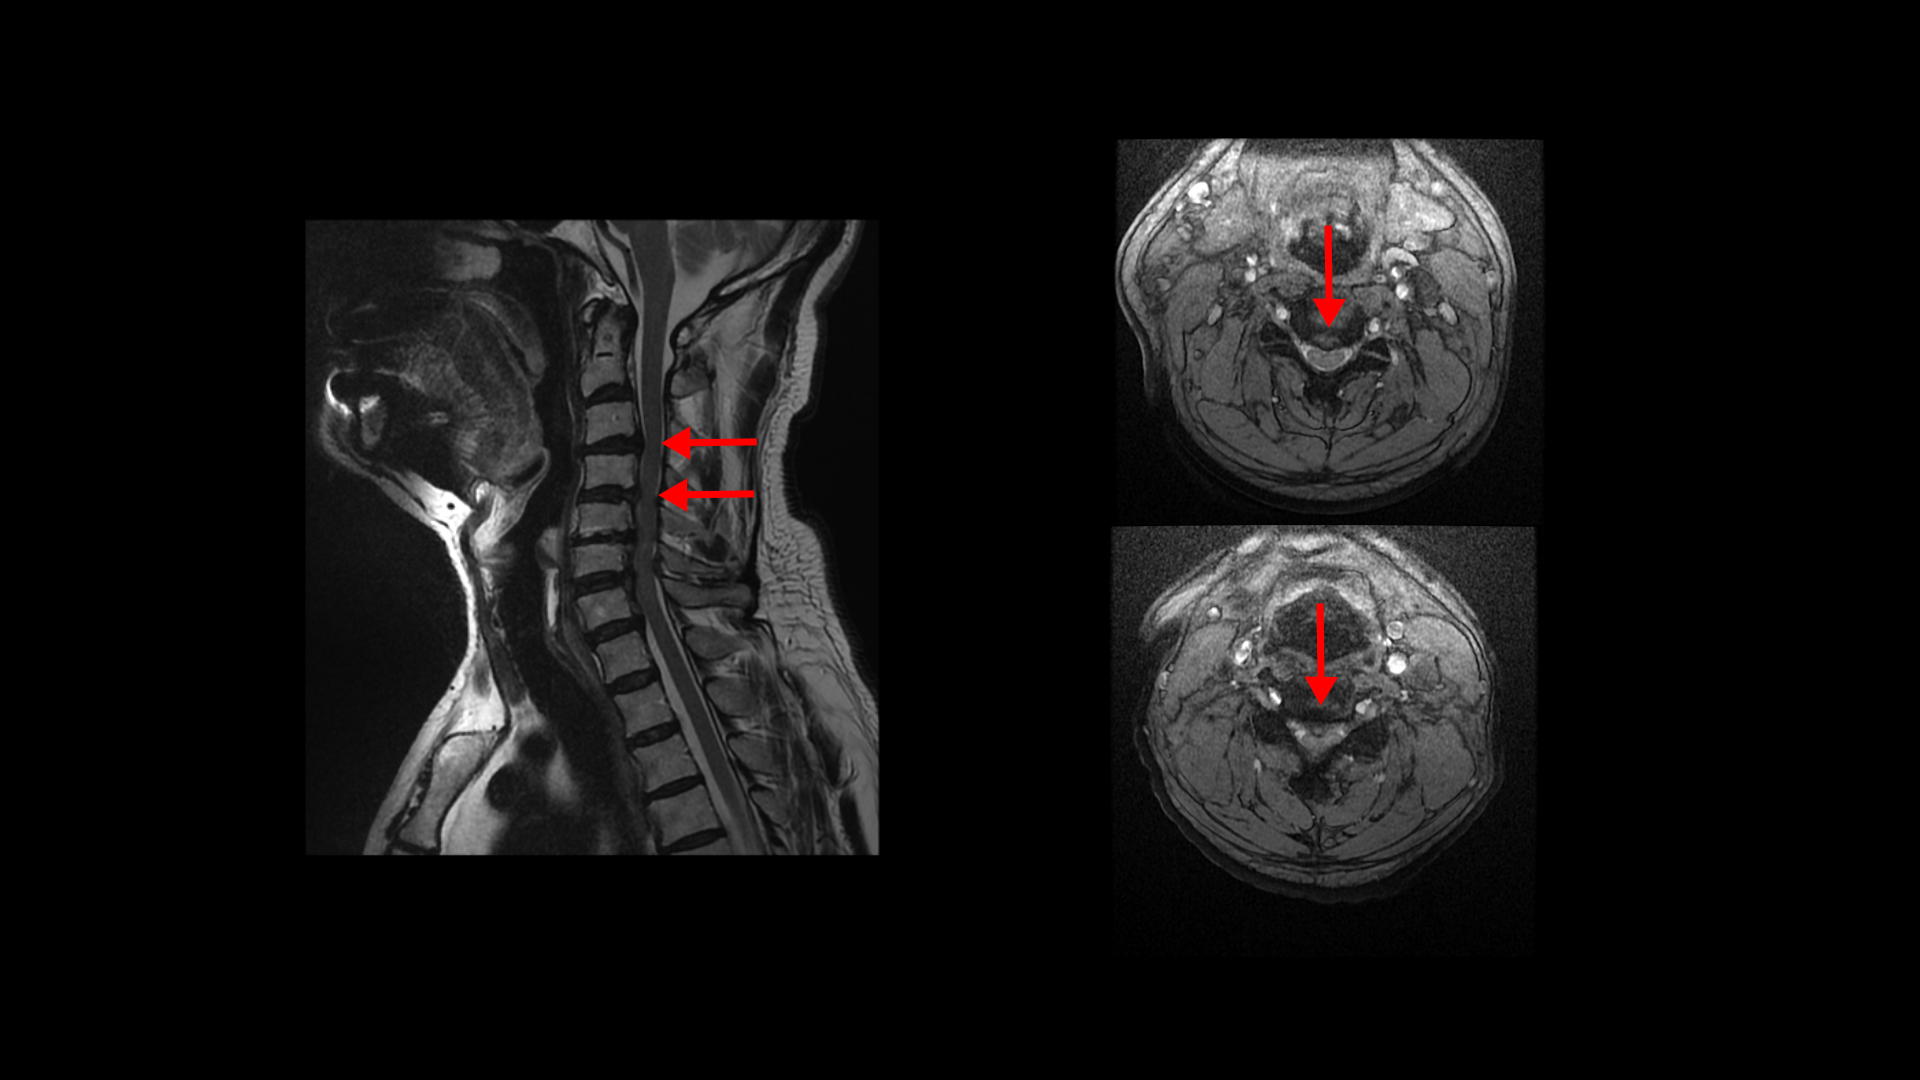

이분 MRI에서 보시다시피 전체적으로 목의 한마디만 제외하고 여러 마디가 다 안 좋습니다.

목의 3번 4번과 4번 5번에는 가운데 쪽으로 디스크 돌출이 있고

5번 6번 문제가 제일 심각한데, 가운데 우측으로 목디스크 파열이 심하게 있습니다.

오른쪽으로 보시다시피 신경 나가는 길이 디스크와 협착으로 많이 막혀 있고 척수 신경에는 경추척수증, 즉 척수신경의 손상이 보입니다.

6번 7번과 7번 흉추 1번 디스크도 가운데로 밀려 나와있습니다.